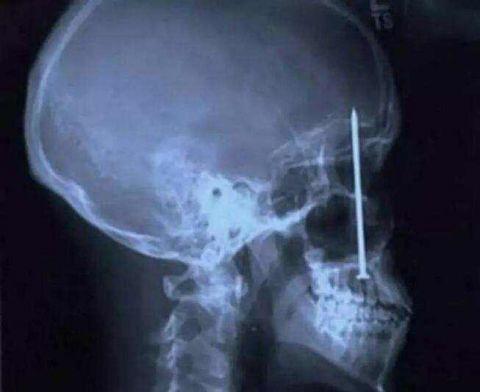

酒吧里面打架被人插得刀子